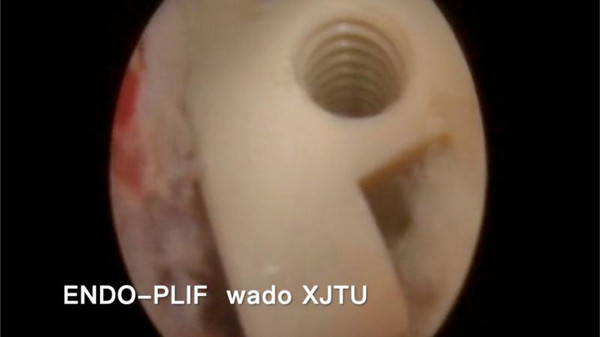

目前临床上针对此型病例,多采用传统的开放手术,即后方入路或椎间孔入路切开减压植骨融合内固定术(PLIF ,TLIF手术)。经治疗组认真讨论,考虑该患者较年轻,治疗组为该患者选择了脊柱内镜下的ENDO-TLIF/PLIF手术。应用脊椎内镜PLUS系统下的腰4/5,腰5/骶1椎间盘切除,椎管减压,植骨融合,经皮后路椎弓根螺钉内固定术,该术式属于内镜下微创手术,通过关节突及椎板的有限磨除,即可达到椎间盘切除及融合固定的手术目的,具有创伤小,早期恢复正常生活。此种术式难度较大,需要一定的脊柱内镜手术经验积累,目前国内仅有少数医院开展。

术中置入椎间融合器

与传统的腰椎后路开放减压手术及通道下的MIS-TLIF手术相比,经脊柱内镜后路腰椎ENDO-TLIF/PLIF手术,创伤更小,神经根及硬膜囊显露清晰,且最大限度的保护了脊柱骨骼、韧带及肌肉的完整性,对脊柱运动单元稳定性影响较小,术后患者感受更佳,康复更快,脊柱的ENDO-LIF微创手术必将成为未来的发展趋势。